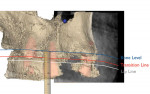

The clinician used a calibrated digital ruler utilizing digital smile design technology to determine maxillary incisal edge position. Normally, the canine cusp tip should be approximately at the same level as, or have up to 1 mm showing below, the upper lip line in repose.11 In this case, the canine was shown to be 2 mm above the upper lip line. By superimposing the smile image and the repose image, the desired canine position was determined; adding 3 mm to the canine would provide an appropriate esthetic result (Figure 6).

Upper lip mobility was measured by superimposing the repose and Duchenne smile photographs and was found to be 6 mm (Figure 7), which is within normal limits.12

The clinician used a video recording of the patient speaking and captured a screenshot with maximum gingival display. Lower lip mobility was measured at 8 mm (Figure 8). The mandibular incisors showed 4 mm in repose, therefore the clinician determined the mandibular incisor position should be reduced in height by 3 mm, leaving a normal 1 mm reveal of the incisal edges in repose.

With the steps above completed, the position of the maxillary and mandibular incisors was established and the upper and lower lip mobility was documented. These measurements allowed the clinician to determine where the gingival tissue-to-restoration interface would be; this is labeled the "transition zone" in the photographs.